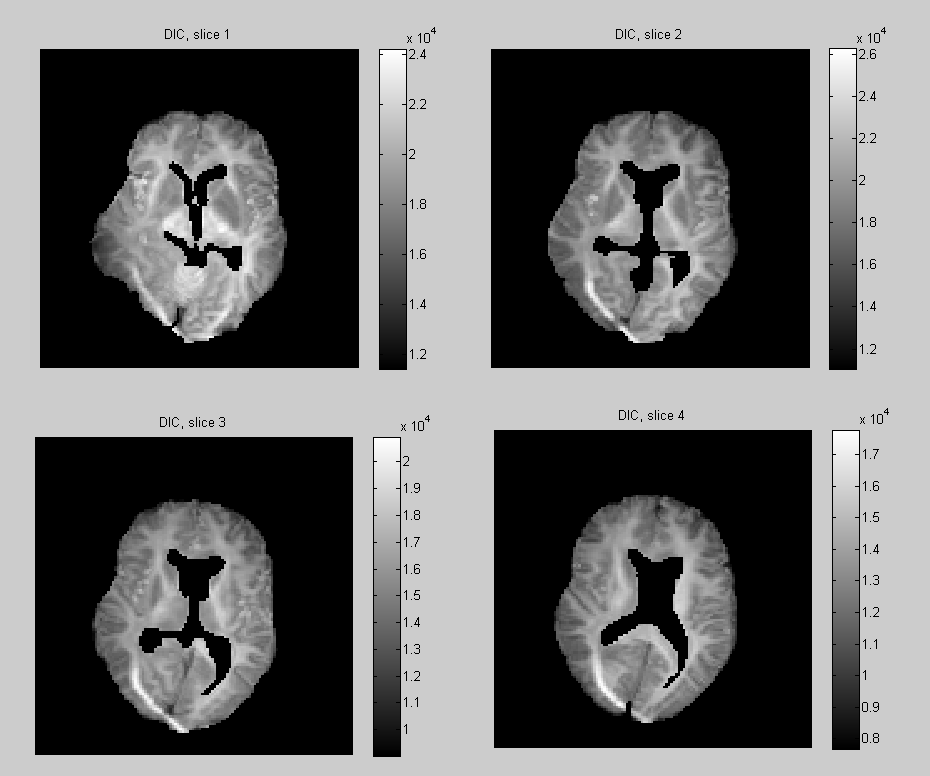

Deviance Information Criterion

This allows for model comparisons, lower DIC meaning a better fit to the data relatively to the effective number of parameters. In Fig. 6 the DIC is computed independently at each voxel under the 2nd and 4th-order tensor models (without regularization). Note that the voxels with the highest DIC corresponds to artefacts where the data is corrupted, and the area of high DIC correspond to complex white matter structures. We also calculated the overall DIC for all voxel under the model 2nd and 4th-order tensor models with regularization. The respective values DIC and DIC, indicate that when we penalize the model by the effective number of parameters, overall the 2th-order tensor model fits our data better than the 4th-order model. In Fig. 7 the posterior expectation of the noise parameters , are shown. When these are interpreted as residual variances in model fitting, we see that they are consistent with the DIC.